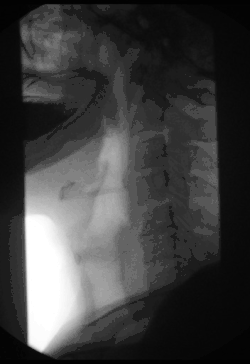

Ösophagusbreischluck

Schluckakt mit Passage des Kontrastmittels und Peristaltik

Kontrastmittel-Röntgenaufnahmen des Ösophagus (Ösophagogramme) und des ösophagogastralen Übergangs ermöglichen sowohl die Tumor-, Ulkus-, Fistel- und Divertikeldarstellung als auch eine Beurteilung des Schluckaktes insbesondere im Hinblick auf neurogene oder muskuläre funktionelle Schluckstörungen.